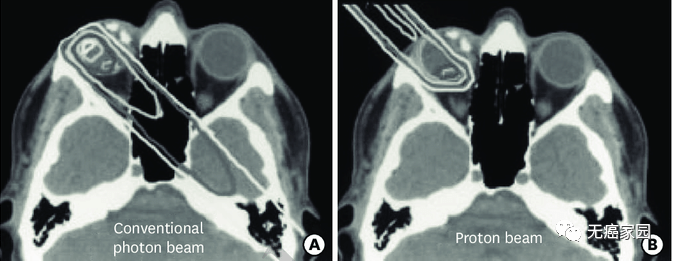

研究结果显示,与传统的光子放射疗法(EBRT)相比,PBRT具有物理优势。在下图的典型病例示意图中,传统光子治疗在眼内靠近肿瘤的部位剂量较大,而且后眼眶和脑内肿瘤远端的剂量也明显高于质子治疗。

左图为常规光子束治疗,右图为质子束治疗研究表明,在维持眼球的情况下,质子束具有比常规光子束更低的辐射剂量,而且最终可以使眼功能最大化。